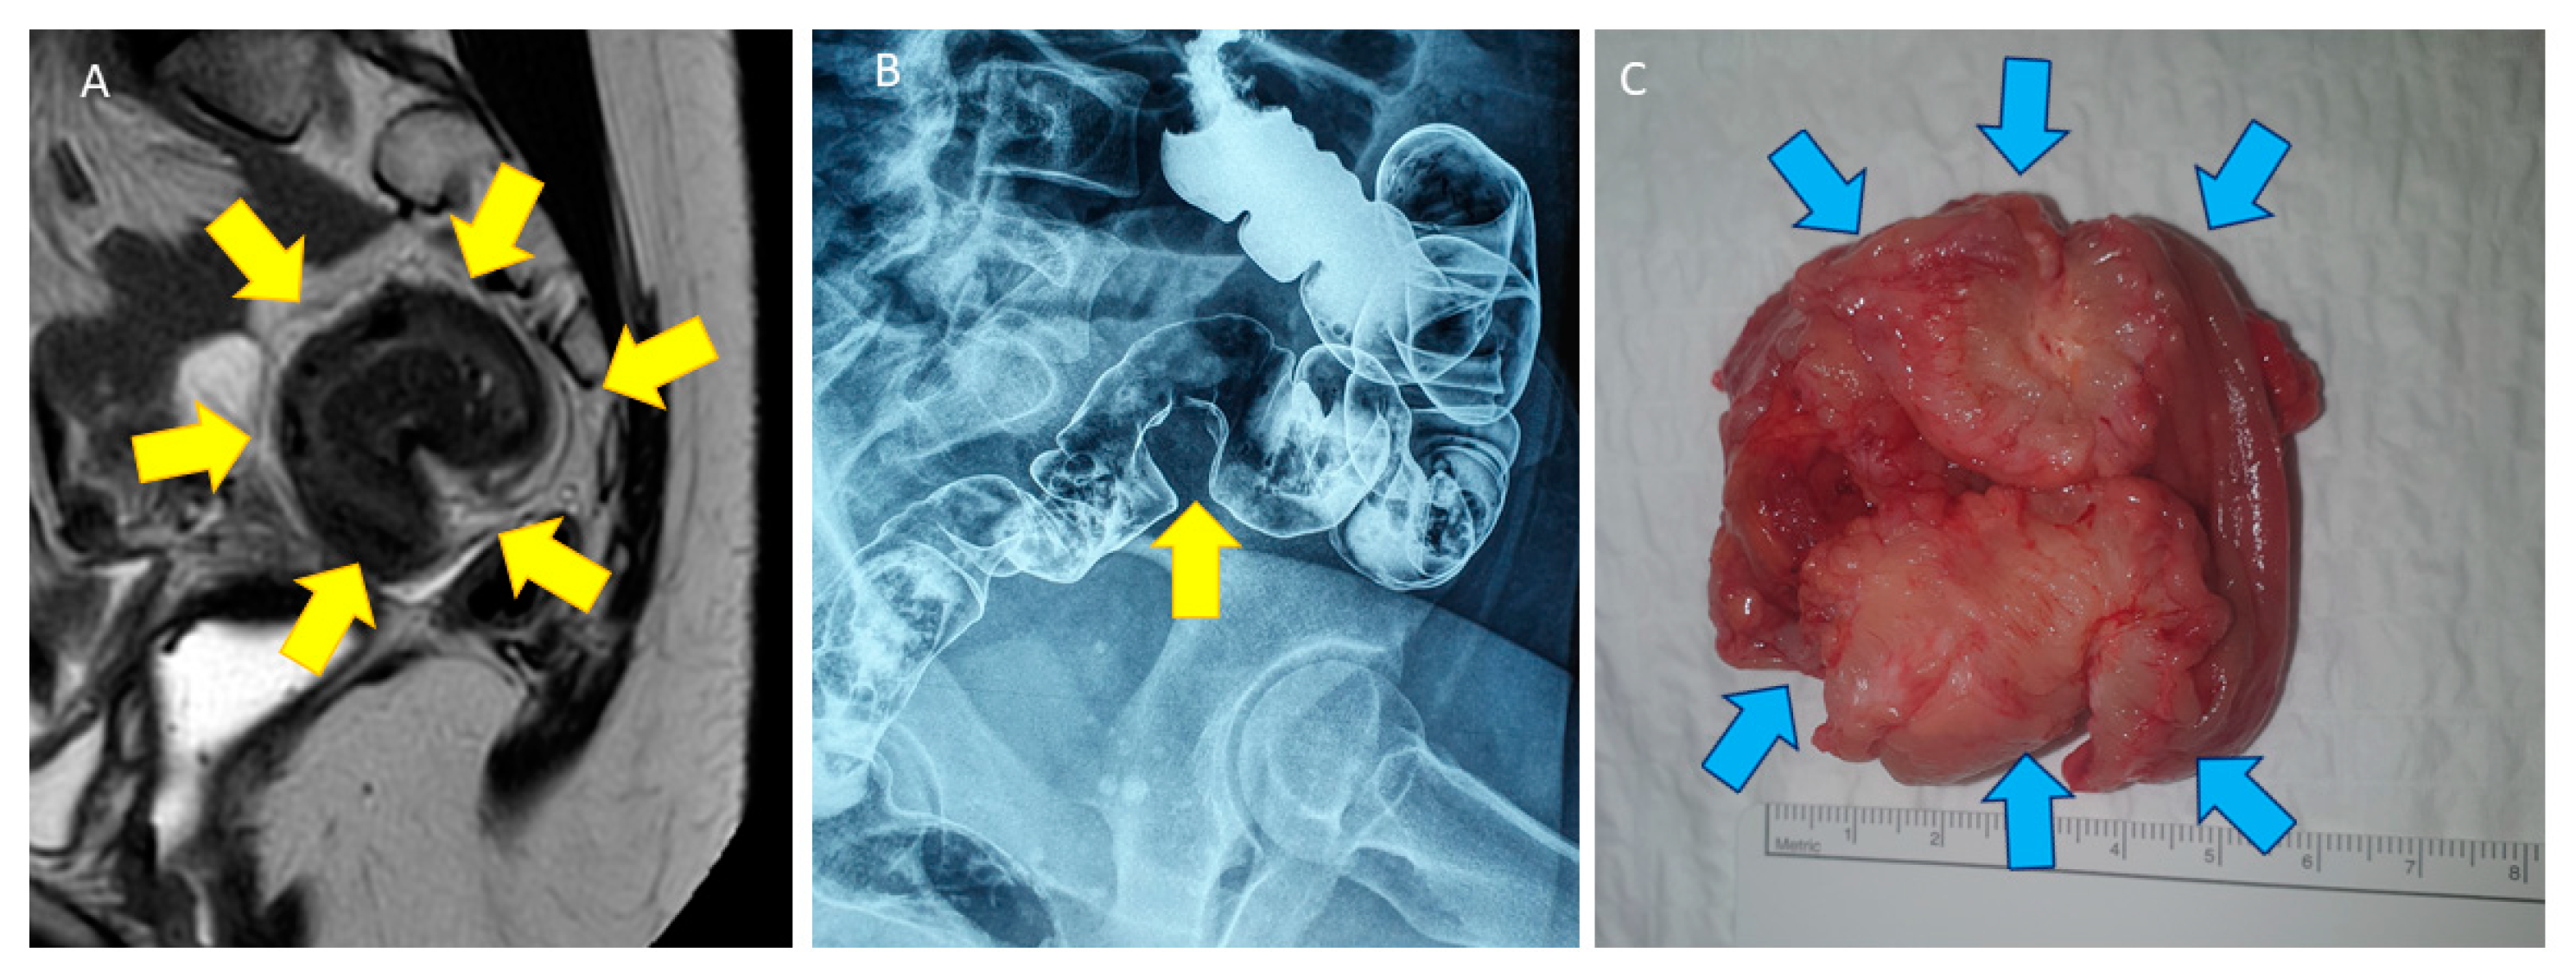

4. Shaving Technique: Surgical Procedure

4.2. Surgical Technique